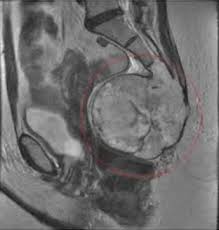

Інфекції, нейропатія, або навіть новоутворення — теж можливі варіанти. Хоч і нечасто, але знайте про таку можливість.